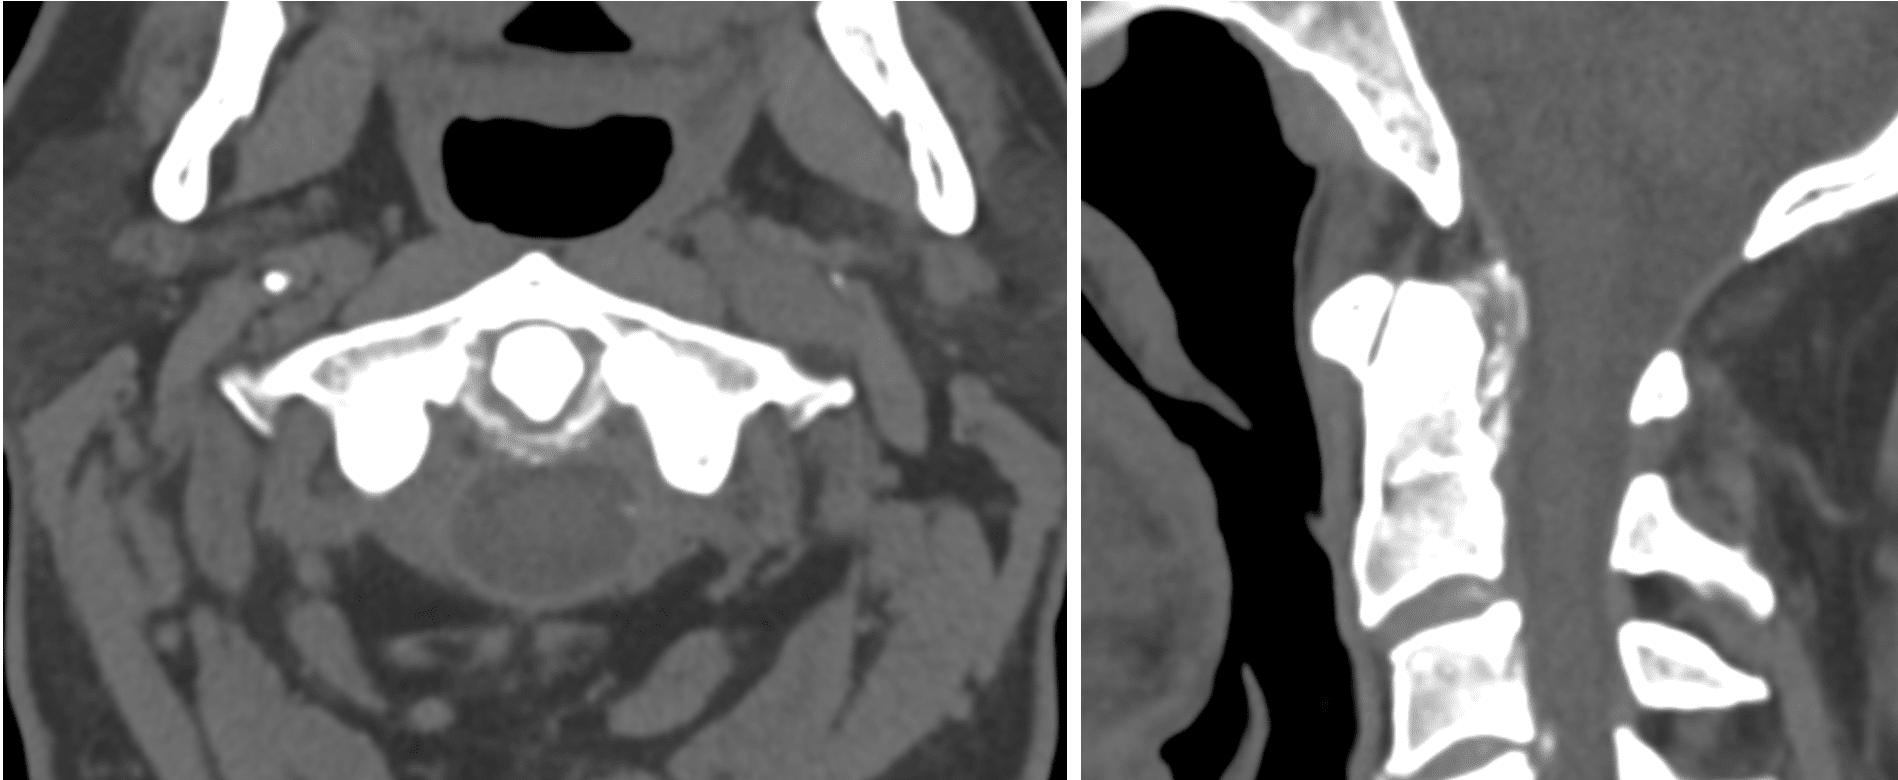

Describe and interpret the CT scan

There is partial periodontal ligament calcification involving the superior, transverse and inferior fibres of the cruciform ligament as well as the alar ligament.

There is mild subchondral sclerosis of the anterior atlantoaxial joint.

High density material around atlantodental interval

Erosion at posterior tip

Widening of the clival odontoid tip

No acute cervical spine fracture.

Satisfactory bony alignment of the craniocervical junction.

No gross cervical spinal malalignment.

Conclusion: Periodontal ligament calcification as described which can be seen in crowned dens syndrome in the appropriate clinical and biochemical context.